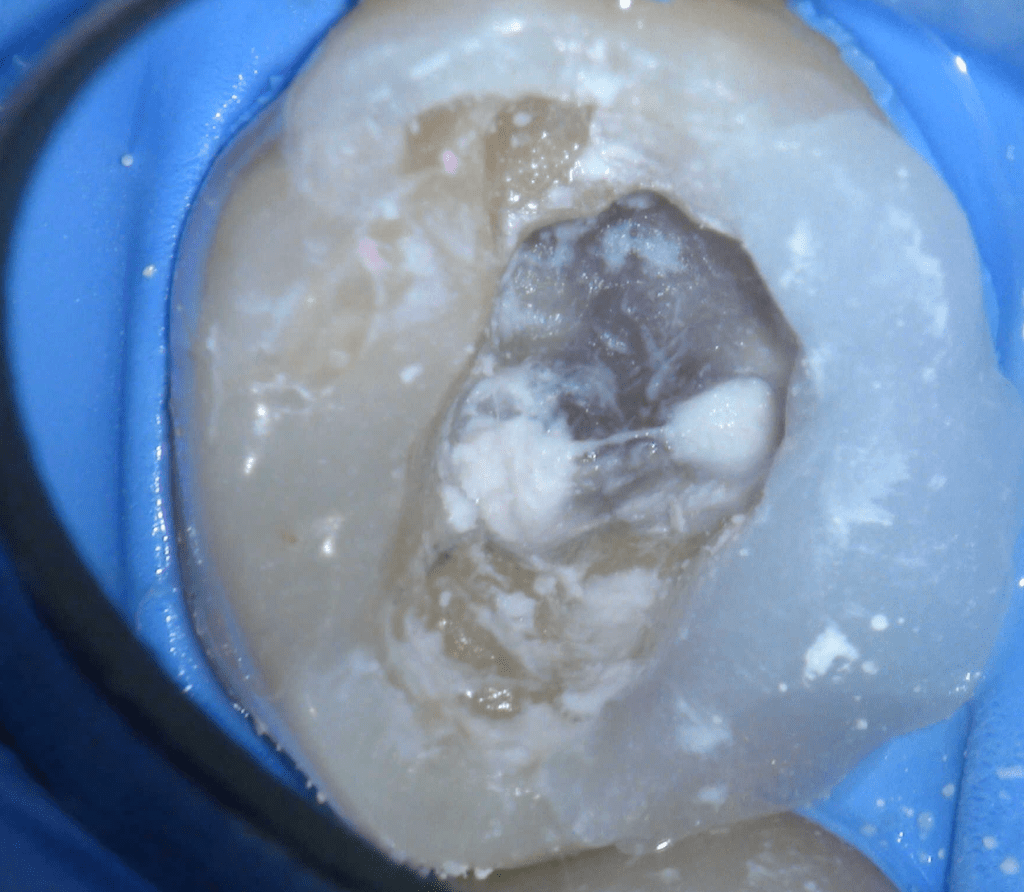

Pulpotomía biodentine + reco preendio